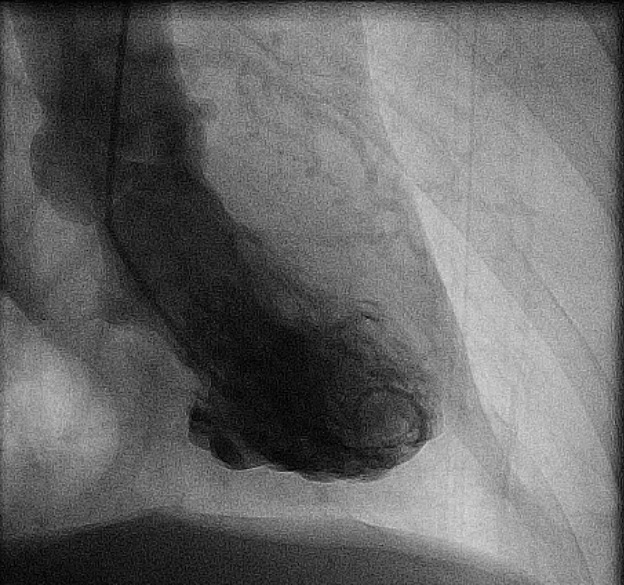

Video 1: Linkerventrikelangiografie

Onderstaande beelden lijken op een Japanse inktvispot

takotsubo diastole

takotsubo systole